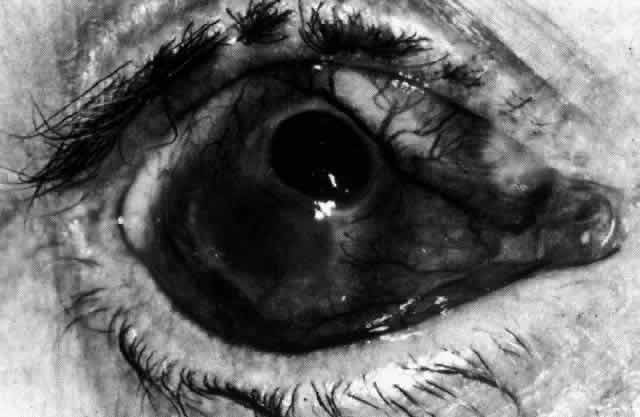

Simple and nodular episcleritis differ in their clinical courses, but in both the edema and infiltration are entirely within the episcleral tissues. The sclera is not involved. The maximum congestion is in the superficial episcleral network, with some slight congestion of the conjunctival vessels and deep episcleral vessels (Fig. 10). The intraocular structures are not involved in either variety, nor is the visual acuity affected. Anterior segment fluorescein angiography reveals a normal vascular pattern but a very rapid flow rate, with the whole transit of the dye being completed within 2 or 3 seconds (Figs. 11 and 12).

Fig. 10. Maximum congestion in the superficial vascular plexus in episcleritis. The conjunctival and deep episcleral networks are separated from the deep plexus by edema and infiltration in the episcleral tissue. (Watson PG, Hayreh S, Awdry P: Episcleritis and scleritis. Br J Ophthalmol 52(3):278–279, 1968)

The redness of simple episcleritis may be intense, varying from a fiery-red or a brick-red discoloration to a mild red flush, but it does not have the bluish tinge that is seen in scleritis. The distribution is usually sectorial but can involve the whole anterior segment of the globe. The episcleral vessels are engorged but retain their normal radial position and architecture (Figs. 13 and 14; Color Plate 1A). In simple episcleritis, there is a diffuse edema of the episcleral tissues. These tissues are sometimes infiltrated with gray deposits that appear yellow in red-free light. Surprisingly, the eye is rarely tender to the touch.